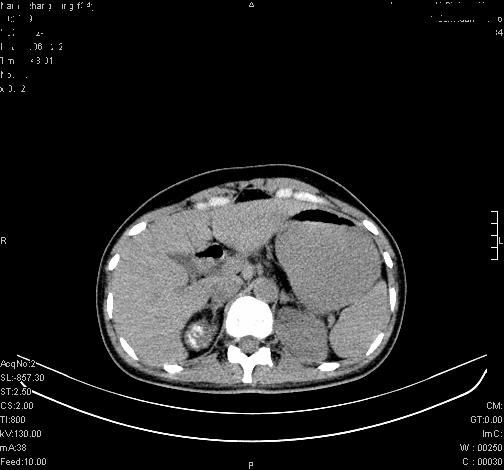

标题: CL0340:【】肾上腺囊肿,比较典型。

患者为年轻女性,查体发现右侧肾上腺囊性占位。无临床体征。

这么漂亮的图像,一看一目了然。典型的右侧肾上腺囊肿,周围有钙化。感谢搂主!

“肾上腺囊肿组织学分为4类:1)内皮细胞性,2)假性囊肿,3)寄生虫性,4)上皮细胞性。其中内皮细胞性最为常见。假性囊肿多为肾上腺内出血后遗留囊腔,囊壁无上皮细胞。寄生虫性多为包虫病引起。上皮性则很少见。”

这么明显的弧形钙化,多考虑包虫病所致的寄生虫性囊肿。

右侧肾上腺囊性密度灶囊壁有钙化。考虑肾上腺囊肿,结核?

右侧肾上腺囊肿,周围有钙化。